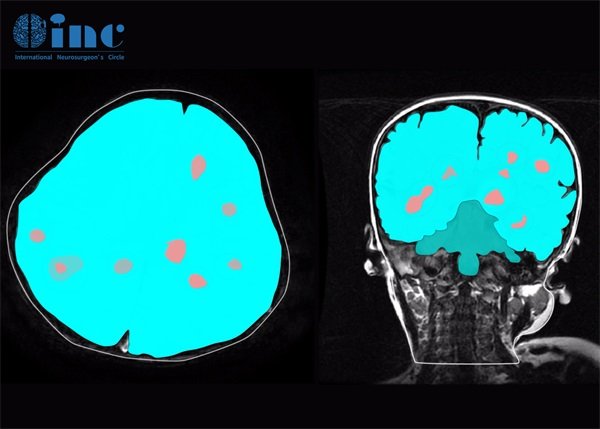

脑部海绵状血管瘤ct影像表现?脑部海绵状血管瘤在CT影像上具有一些独特的表现。通常表现为低密度区,给人以"海绵状"的外观。该病变的边界相对清晰,质地较软,内容物多为血液及增生的血管。在增强扫描中,海绵状血管瘤的血管结构会明显强化,这是其显著的特点之一。脑部海绵状血管瘤是一种良性的血管性肿瘤,通常发生在脑内血管系统中。这种病变的特点是在影像学上具有特征性的表现,尤其是在CT扫描中。

脑部海绵状血管瘤在CT影像上具有一些独特的表现。通常表现为低密度区,给人以"海绵状"的外观。该病变的边界相对清晰,质地较软,内容物多为血液及增生的血管。在增强扫描中,海绵状血管瘤的血管结构会明显强化,这是其显著的特点之一。

此外,在某些情况下,病灶可能出现环状增强,这主要是由于周围组织的反应性改变,提供了额外的诊断线索。通常,海绵状血管瘤的大小可以从几毫米到几厘米不等,而较大的病变更易于在CT上被识别。

海绵状血管瘤常见于脑半球,尤其是额叶、顶叶和枕叶,少见于小脑和脑干。根据统计数据,不同年龄阶段及性别的人发病率可能有所不同,年轻人更易受到影响,而女性的发病率相对较高。